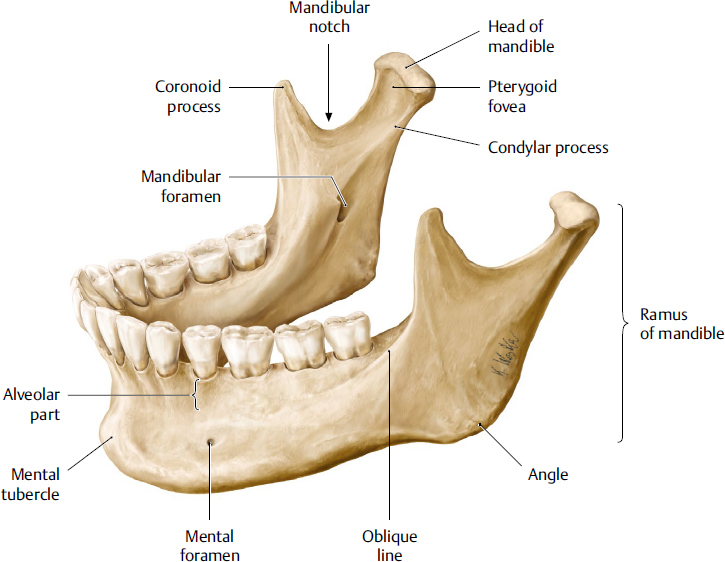

1.

Amalgam

Opening or hole in bone located on the external surface of the mandible in the region of the mandibular premolars.

Radiolucent/Radiopaque?

Mental foramen

Radiolucent